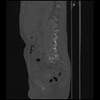

7 CUERPO,CE,Sagittal,3.000,CUERPO,Sagittal,